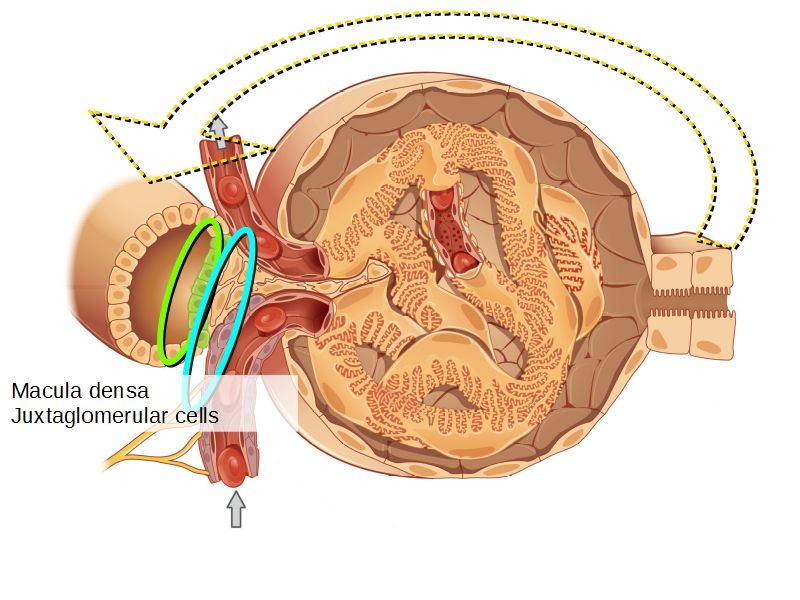

Juxtaglomerular complex

Area where distal convoluted tubule return to glomerulus and pass through the notch between the afferent and efferent arterioles. Modification of the wall of the tubule and afferent arteriole and presence of specialised cells in the connective tissue.